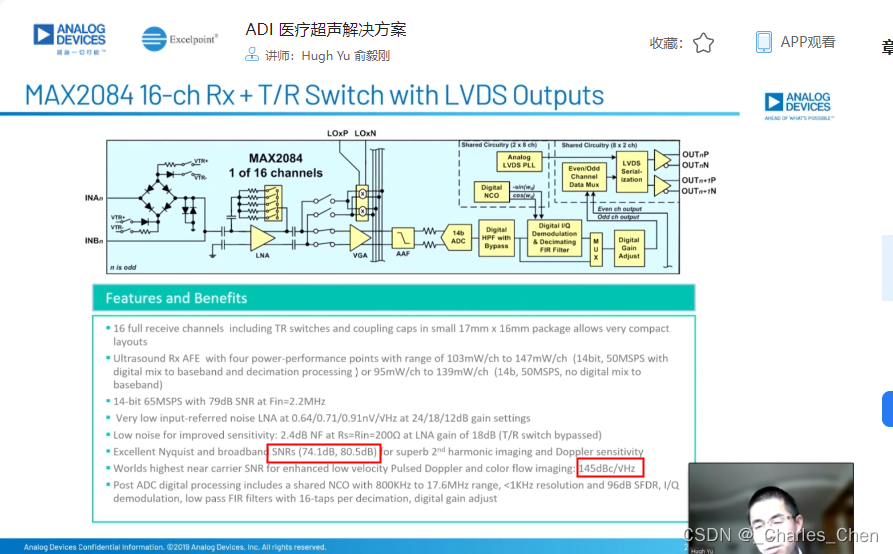

成像通道接收机

超声成像通道的接收机用于检测二维(2D)信号以及彩超流体成像所需的脉冲多普勒(PWD)信号和频谱PWD。接收机包括Tx/Rx开关、低噪声放大器(LNA)、可变增益放大器(VGA)、抗混叠滤波器(AAF)和模/数转换器(ADC)。

Tx/Rx开关

低噪声放大器(LNA)

可变增益放大器(VGA)

抗混叠滤波器(AAF)和ADC

典型应用中采用12位ADC,采样率通常在40Msps至60Msps之间。ADC提供必要的瞬态动态响应范围,同时具有适当的成本和功耗。在设计得当的接收器中,ADC会限制接收通道的瞬态SNR。如上所述,性能差的VGA会限制整个接收通道的SNR指标。